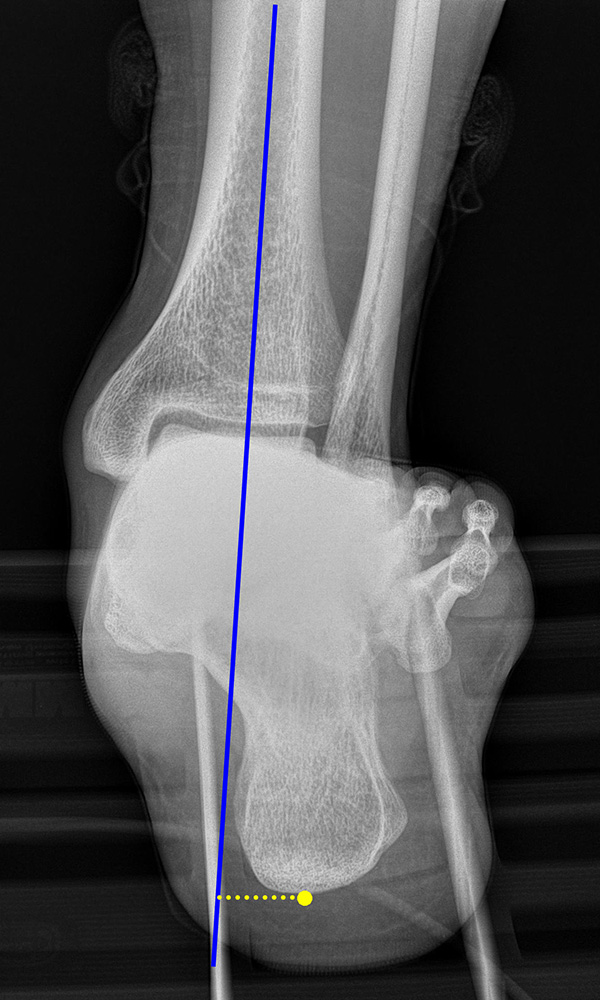

Saltzman Rückfußachsaufnahme (Hindfoot alignment view)

Rückfuß-Alignement-Aufnahmen sind eine wichtige Ergänzung zur Diagnostik von Kalkaneusfehlstellungen (Varus und Valgus), sowie bei der Planung von Rückfußkorrekturen 14.

Kennzeichen des Röntgenbildes:

• Markieren der Tibiaachse mit Verlängerung nach distal.

• Der funktionelle Hebelarm des Kalkaneus errechnet sich aus der Distanz zwischen der Tibiaachse und dem am weitesten plantar gelegenen Punkt des Kalkaneus.

• Liegt der tiefste Punkt des Kalkaneus medial der Tibiaachse, handelt es sich um eine Varus-Stellung, liegt er lateral, um eine Valgus-Stellung.

• Norm: Auftrittspunkt 3,2 ± 8 mm medial der Tibiaachse 14.